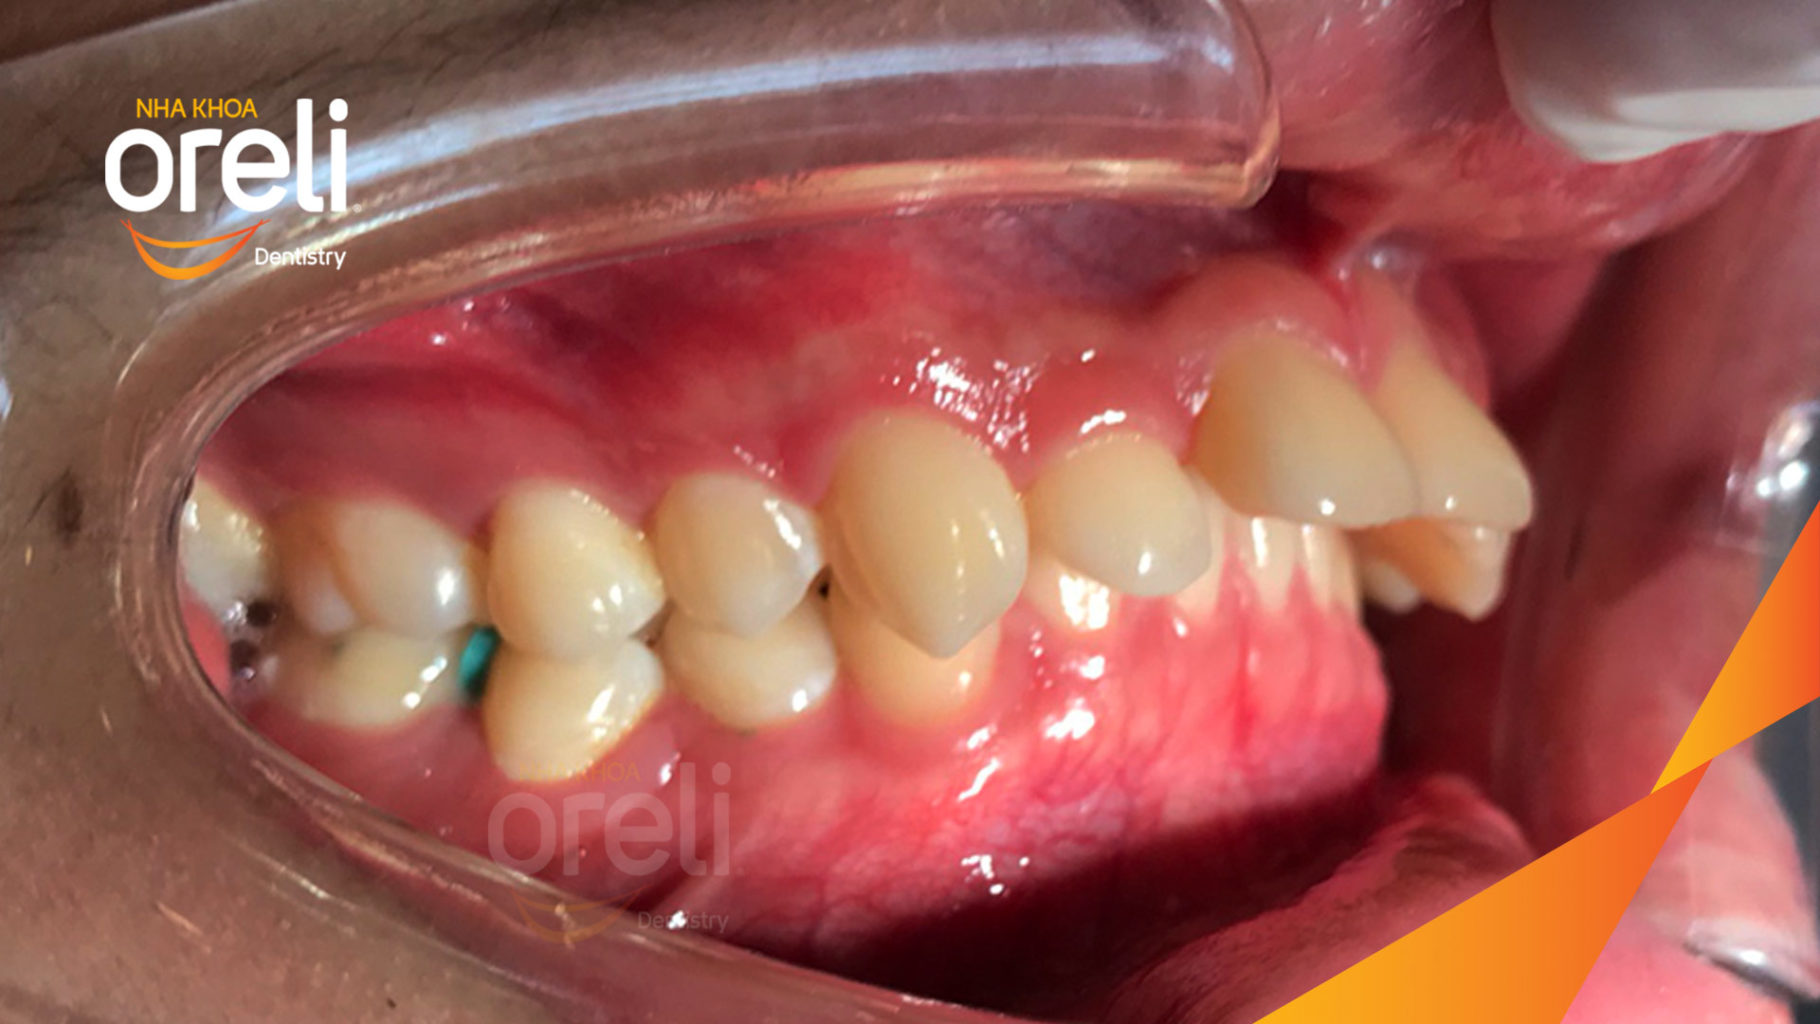

Ca niềng chỉnh cắn sâu hô lùi cằm cho kết quả nụ cười và góc nghiêng đẹp ở Oreli

Ca niềng răng cắn sâu phục hồi ăn nhai và thẩm mỹ nụ cười. Kết quả thực tế trước và sau điều trị tại Nha khoa Oreli.

Giải pháp: làm đều chỉnh khớp cắn sâu không nhổ răng

Thời gian: 36 tháng

Kết quả: khớp cắn đúng, cằm tiến ra trước với mặt nghiêng đẹp